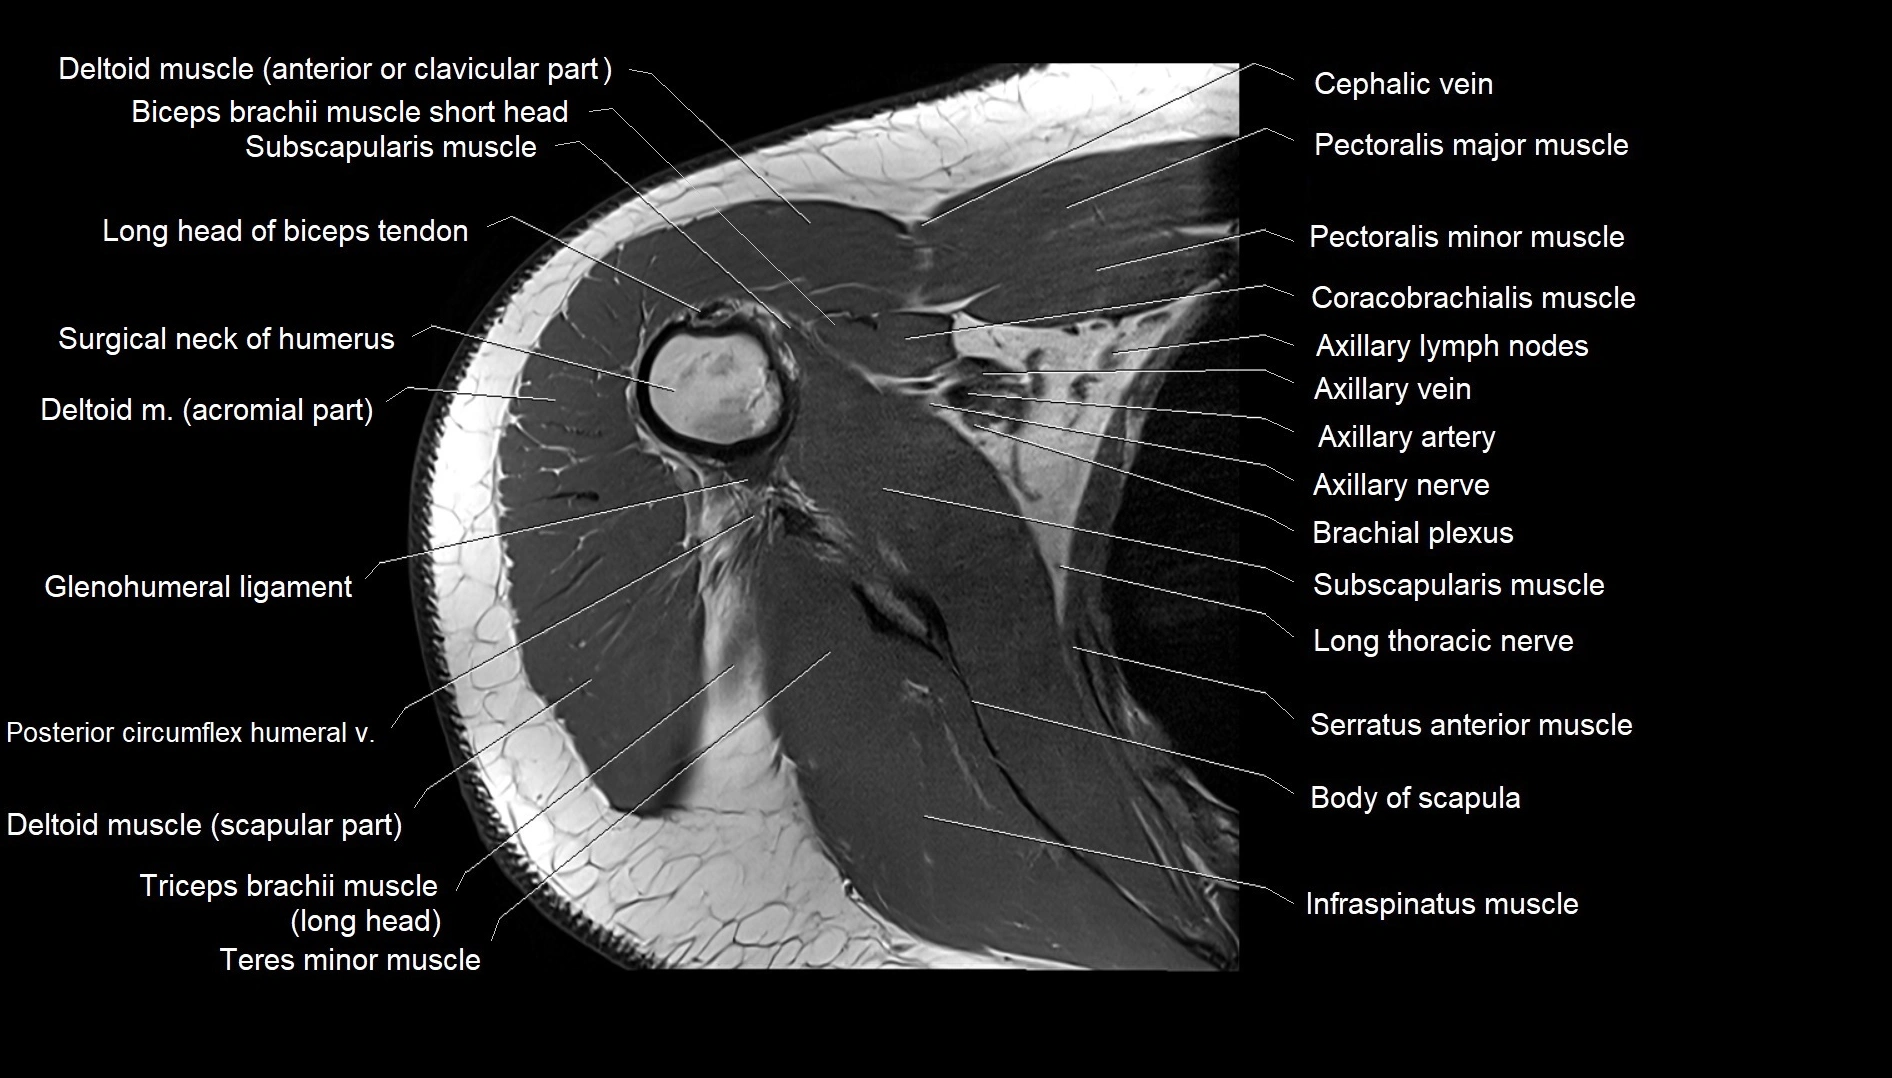

TEST YOURSELF

Fullscreen Image